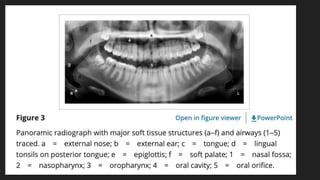

OTHER STRUCTURES

LANDMARKS WHICH APPEAR AS RADIOPAQUE:

· Tongue

· Soft palate

· Uvula

· Ear

· Lip Line

LANDMARKS WHICH APPEAR AS RADIOLUCENT:

· Palatoglossal air space

· Nasopharyngeal air space

· Glossopharyngeal air space

POINTS FOR STRUCTURES:

1. Tongue: It appears as a radiopaque area superimposed over the posterior maxillary teeth.

2. Soft palate and uvula: It is represented as radiopacity located diagonally posteriorly and

inferiorly from the maxillary tuberosity region.

3. Lipline: It is seen in the anterior teeth region. The areas of the teeth covered by lips appear

more radiopaque.

4. Ear: It is marked as a radiopaque shadow that projects anteriorly and inferiorly from the

mastoid process.

5. Palatoglossal air space: It appears as a radiolucent band located above the apices of the

maxillary teeth.

6. Nasopharyngeal air space: It is a diagonal radiolucent band located superior to the radiopaque

shadow of the soft palate and uvula.

7. Glossopharyngeal air space: It is a vertical radiolucent band superimposed over the

mandibular ramus.

8. The epiglottis can often be seen as a thin finger-like projection extending from the posterior

tongue, below the angles of the mandible